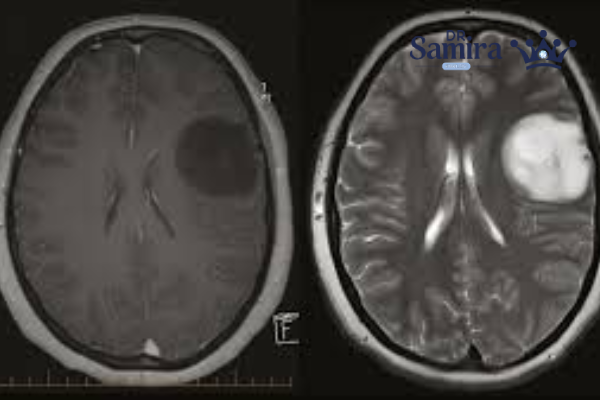

تصویربرداری مغزی و نخاعی با MRI بهترین گزینه برای تشخیص است. این روش می‌تواند محل، اندازه، ارتباط با بافت‌های مجاور و احتمال گسترش را نشان دهد. برای مواردی که تومور واقع در ناحیه مغزی است، پس از جراحی و در پیگیری‌ها نیز MRI دوره‌ای کاربرد دارد. در برخی مطالعات نوظهور، روش‌های رادیومیک (Radiomics) و یادگیری ماشینی روی تصاویر MRI برای کمک به درجه‌بندی تومورها مورد بررسی قرار گرفته‌اند. اگرچه بیشتر این مطالعات روی گلیوماها انجام شده‌اند نه صرفاً اپاندیموم، می‌توان به چشم یک گرایش آینده‌نگر نگاه کرد.